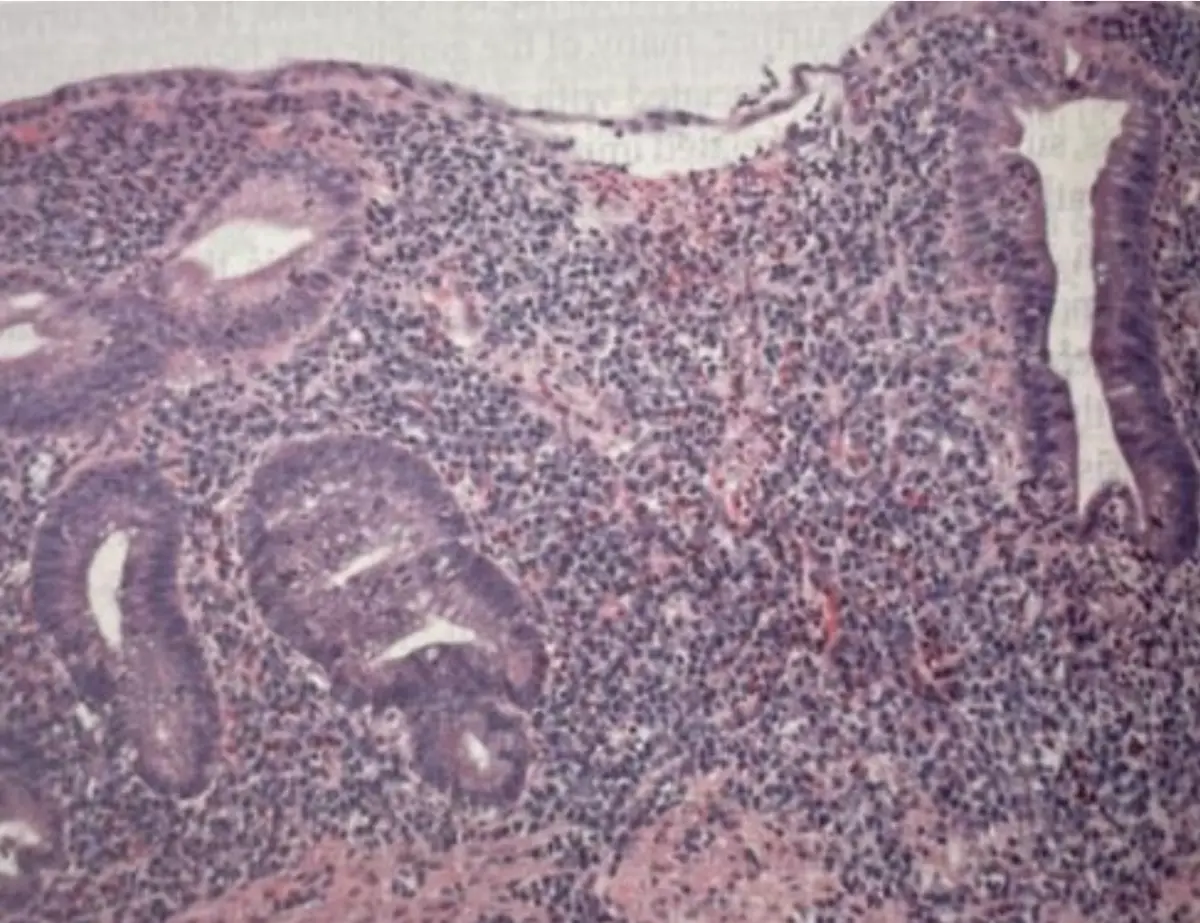

23 歲男性糞便帶黏液與血,結腸鏡見持續性黏膜發炎,病理切片呈現腺窩膿瘍及黏膜層大量發炎細胞浸潤,典型為 ulcerative colitis。題幹考點集中在 ulcerative colitis 的流行病學與已知環境危險(或保護)因子。

2. 組織切片 (H&E):僅限於黏膜層的密集發炎細胞(多為中性球、漿細胞),腺體變形並有腺窩膿瘍,無肉芽腫、無全層炎症,支持 ulcerative colitis 而非 Crohn disease。